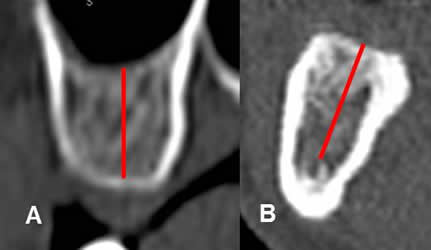

Fig 24. Altura de la cresta ósea.

A: TAC reconstrucción transversal del maxilar y B: de la mandíbula.

Altura del hueso, entre el borde superior e inferior de la cresta alveolar. En la mandíbula, el borde inferior corresponde al canal mandibular.

Fig 25. Ancho de la cresta ósea.

A: TAC reconstrucción transversal del maxilar y B: de la mandíbula. Ancho del hueso, medido entre los bordes internos de las corticales, en la región mas estrecha.